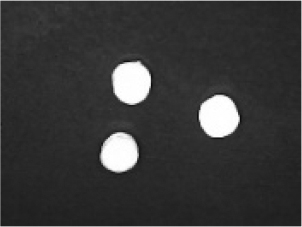

In addition to the disintegration endpoint studied using the USP disintegration apparatus, the pellets disintegrated into particles of various sizes when evaluated at a static position. A few drops of water were placed on the pellets on the opaque surface. A USB digital microscope (China) was connected to a computer to capture the disintegration process. Images were captured from the beginning until the pellet disintegrated or exploded into small fragments. Pellet images were acquired every 30 seconds. for formulations containing polyplasdone XL 10 and croscarmellose sodium.

Disintegration was evaluated at room temperature under static conditions. The camera captured images every 30 s ( Table 9), illustrating that MCC pellet X3 with mannitol and PEG 400 did not disintegrate. Within 120 s, cracks appeared in P5 pellets containing mannitol, PEG, and PPXL. As seen in the C4 pellets, they begin to explode into many fragments within 30 s. Moreover, the CP12 pellets containing PEG 400, mannitol, CCS, and PPXL began to explode into many loosely linked particles after 60 s, which quickly separated under the oscillating motion of the USP disintegration equipment. The photographs are compatible with the results mentioned above for the USP disintegration device. When the temperature was increased to 37°C, the disintegration caused the split into tiny fragments.

Table 9. Camera capture of pellet disintegration at different time intervals.

Pellet # 0 sec. 30 sec. 60 sec. 90 sec. 120 sec.

X3c9c3975f-9288-4951-a800-a8e9fc463382_GRA58.gif c9c3975f-9288-4951-a800-a8e9fc463382_GRA59.gif c9c3975f-9288-4951-a800-a8e9fc463382_GRA60.gif c9c3975f-9288-4951-a800-a8e9fc463382_GRA61.gif c9c3975f-9288-4951-a800-a8e9fc463382_GRA62.gif